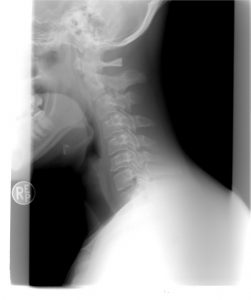

Dla osób, cierpiących na bóle szyi oraz karku, polecane jest proste ćwiczenie Rolanda Brachta, dzięki któremu można w krótkim czasie uwolnić się od napięcia. Nie trzeba więc znosić cierpień – pomoc jest w naszych rękach, a ulga może przyjść prawie natychmiast.

Siadamy na krześle, trzymając plecy prosto. Dłonie kładziemy na czubku głowy, mając cały czas widok przed sobą. Trzymając dłonie na głowie, wykonujemy ostrożne podciągnięcie szyi do delikatnego zgięcia ku przodowi.

Po przyjęciu tej pozycji możemy poczuć delikatne pieczenie na karku oraz stopniowo odczuwać rozciąganie się szyi oraz niższych partii ciała. Ręce trzymamy cały czas luźno na głowie, nie próbując przyciągać nimi głowy do przodu. Przy wydechu można próbować przemieścić głowę odrobinę niżej, jednak bez jakiegokolwiek nacisku.

Uwaga: Plecy powinny być przez cały ten czas wyprostowane, a przeciąganie powinno być powodowane wyłącznie przez ułożone na głowie ręce. Warto zadbać o osobę, która będzie obecna podczas wykonywania ćwiczeń – pomoże nam ona w kontrolowaniu pozycji pleców.

Kiedy głowa znajdzie się w najniższej pozycji, należy zostawić na niej wyłącznie lewą rękę. Prawą kładziemy w tym momencie na ramieniu, gdy jest zgięta w łokciu; następnie lekko ciągniemy do tyłu. Należy wykonać ten ruch ostrożnie, tak, by nie przechylić głowy na bok. Oddychamy głęboko i zmieniamy strony.